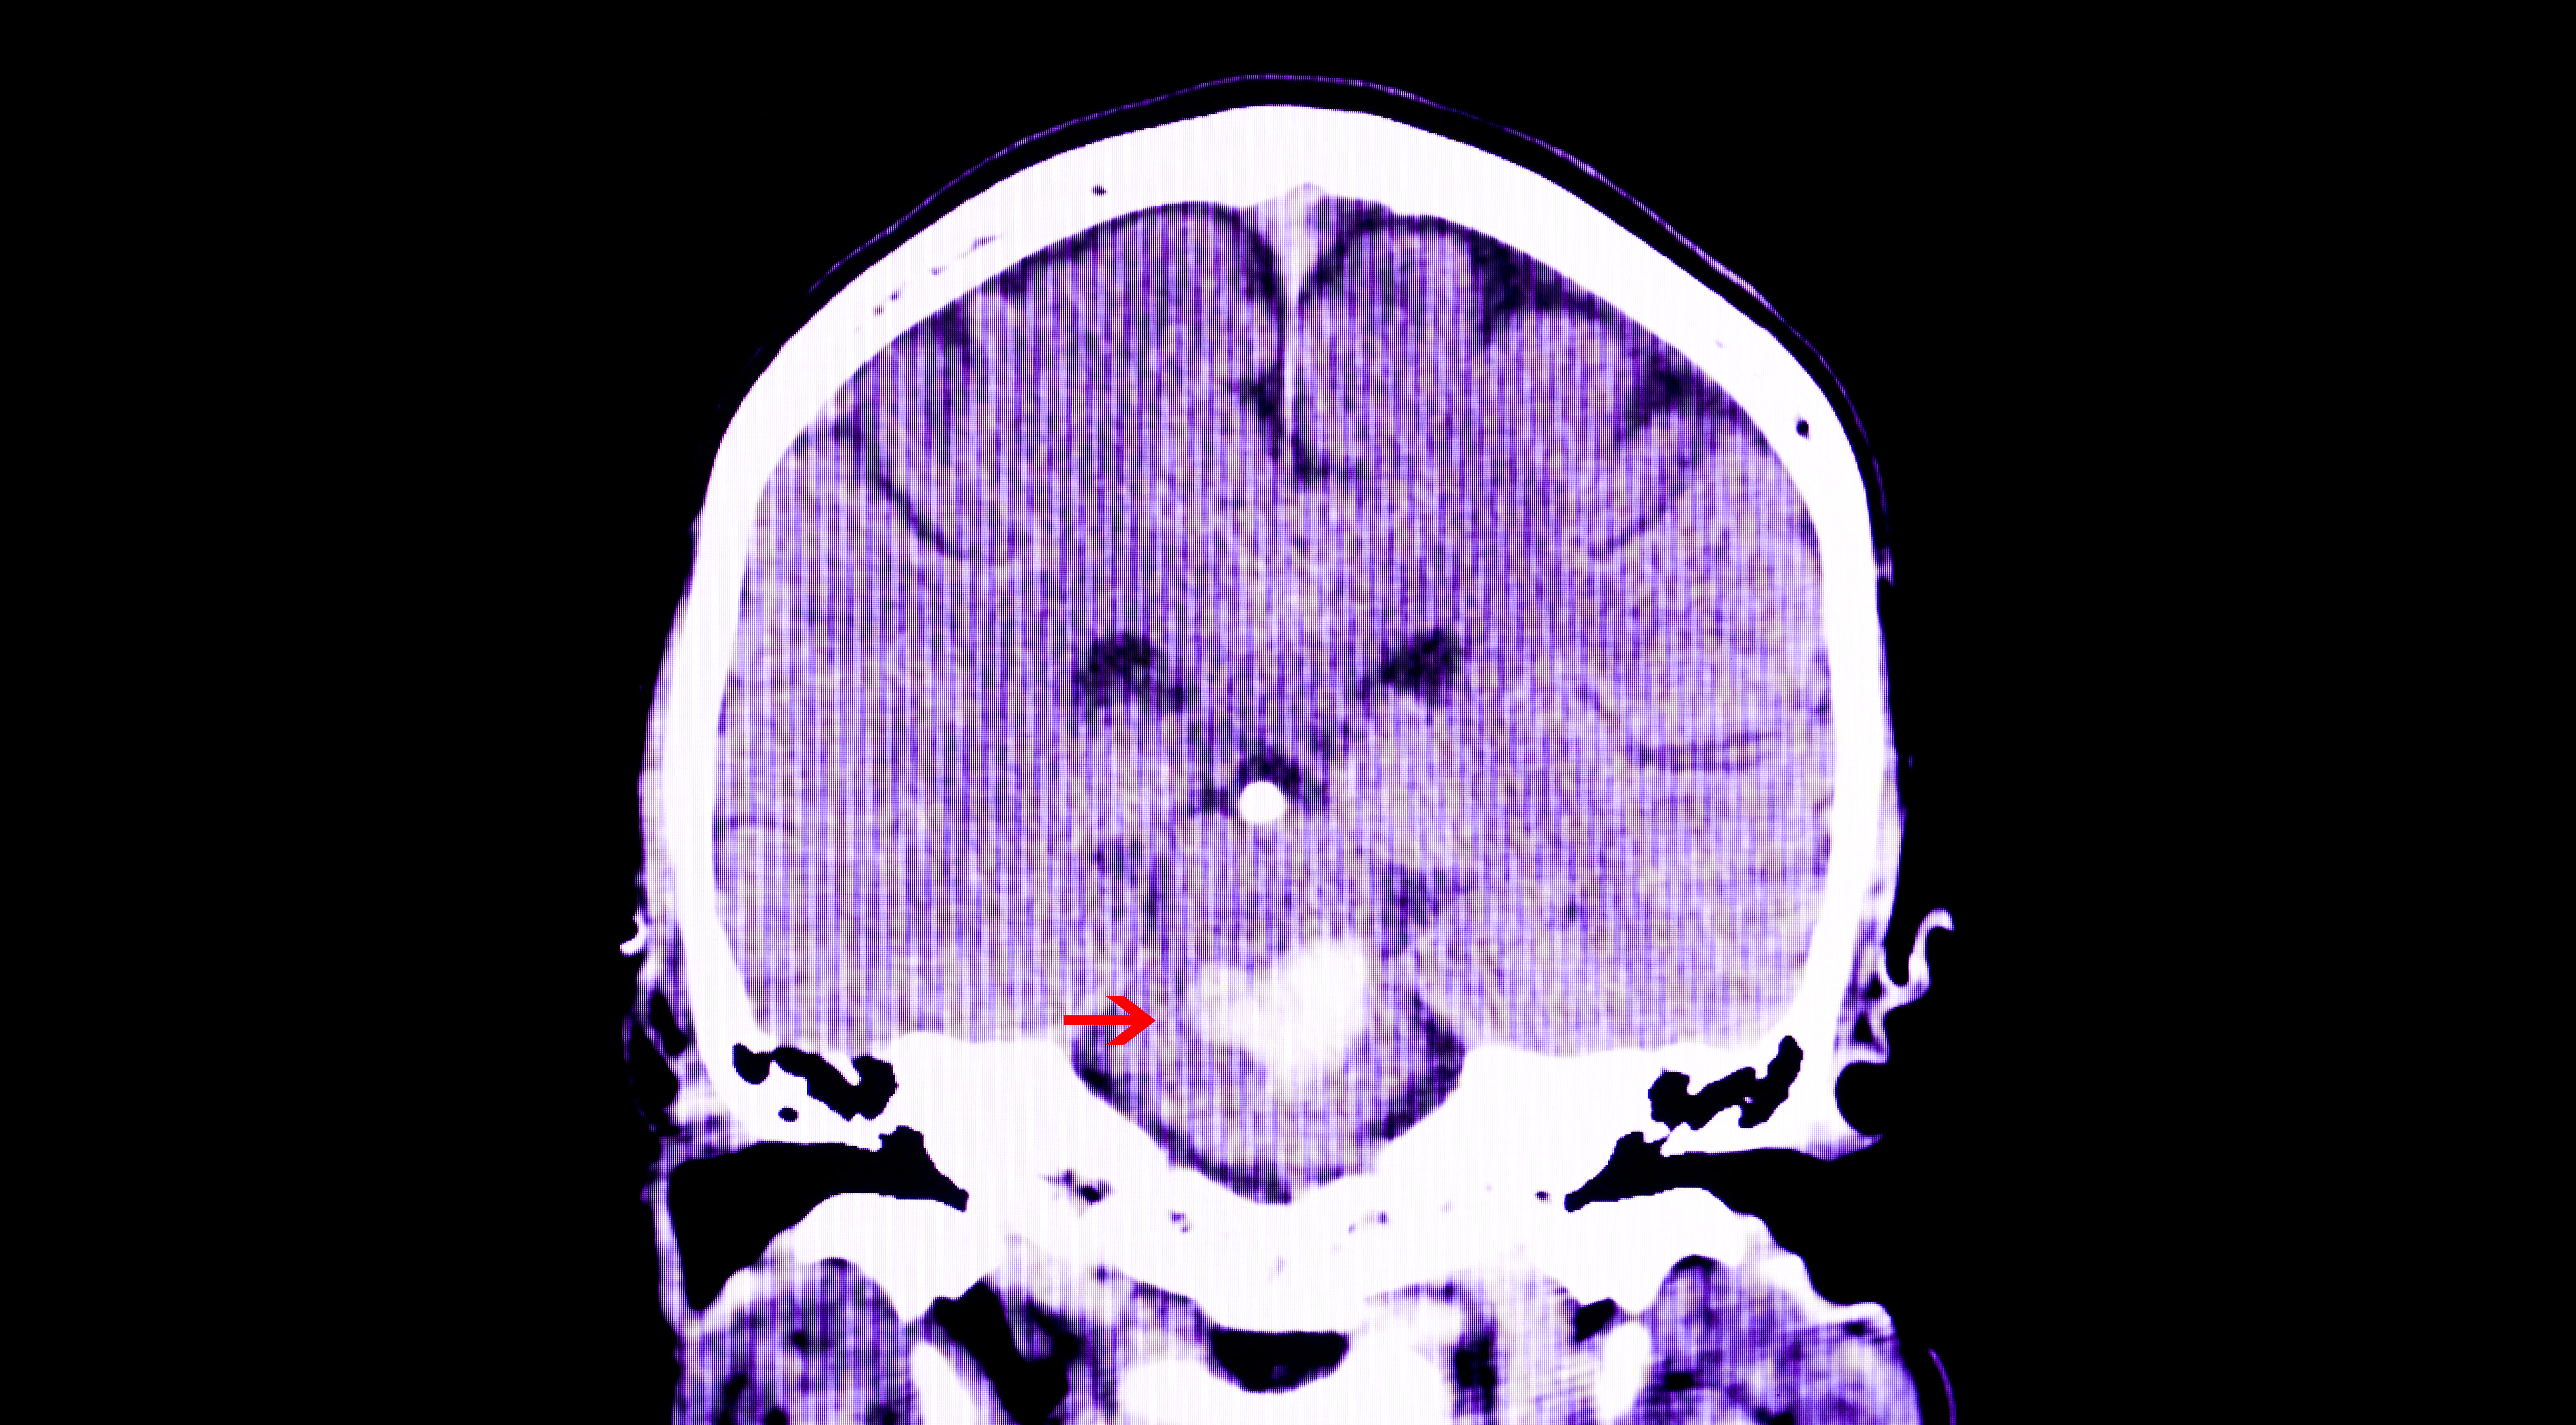

El diagnóstico a tiempo de un ACV comienza con una valoración clínica detallada, donde el equipo médico identifica los síntomas y realiza un examen neurológico. Luego, se utilizan herramientas como la tomografía computarizada (TC) y la resonancia magnética (RM) cerebral para saber qué tipo de ACV es y dónde está ubicado el daño. En algunos casos, también se piden exámenes de sangre, electrocardiogramas o ecocardiografías para buscar la causa exacta.

En Bogotá, instituciones aliadas a la Pontificia Universidad Javeriana cuentan con protocolos de atención rápida para pacientes con sospecha de ACV. Esto incluye la activación de equipos multidisciplinarios y acceso a tecnología avanzada para realizar diagnósticos precisos. La correcta interpretación de los estudios de imagen es vital para decidir el tratamiento más adecuado y minimizar riesgos.